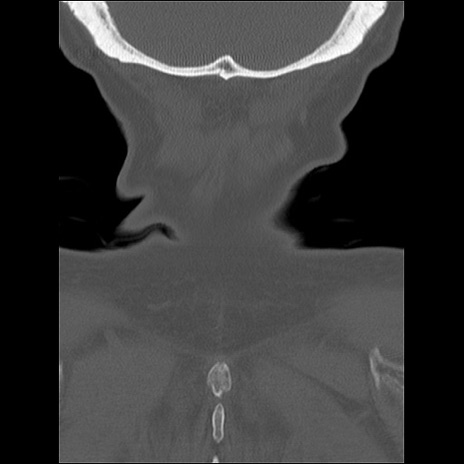

症例48 頚椎CT(冠状断像)

頚椎CT